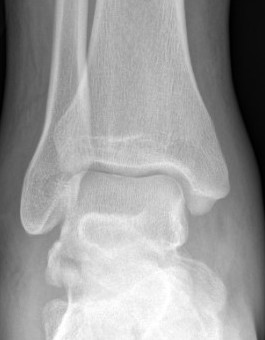

X-ray

Best seen on mortise view

McCrory-Bladin Classification

| Type I |

Type 2A |

Type 2B | Type 3 |

|---|---|---|---|

|

Chip fracture Doesn't involve articular surface |

Larger fracture Involves articular surface talofibular & subtalar join Undisplaced |

Larger fracture Involves articular surface talofibular & subtalar joint Displaced |

Comminuted fracture Involves articular surface talofibular & subtalar |